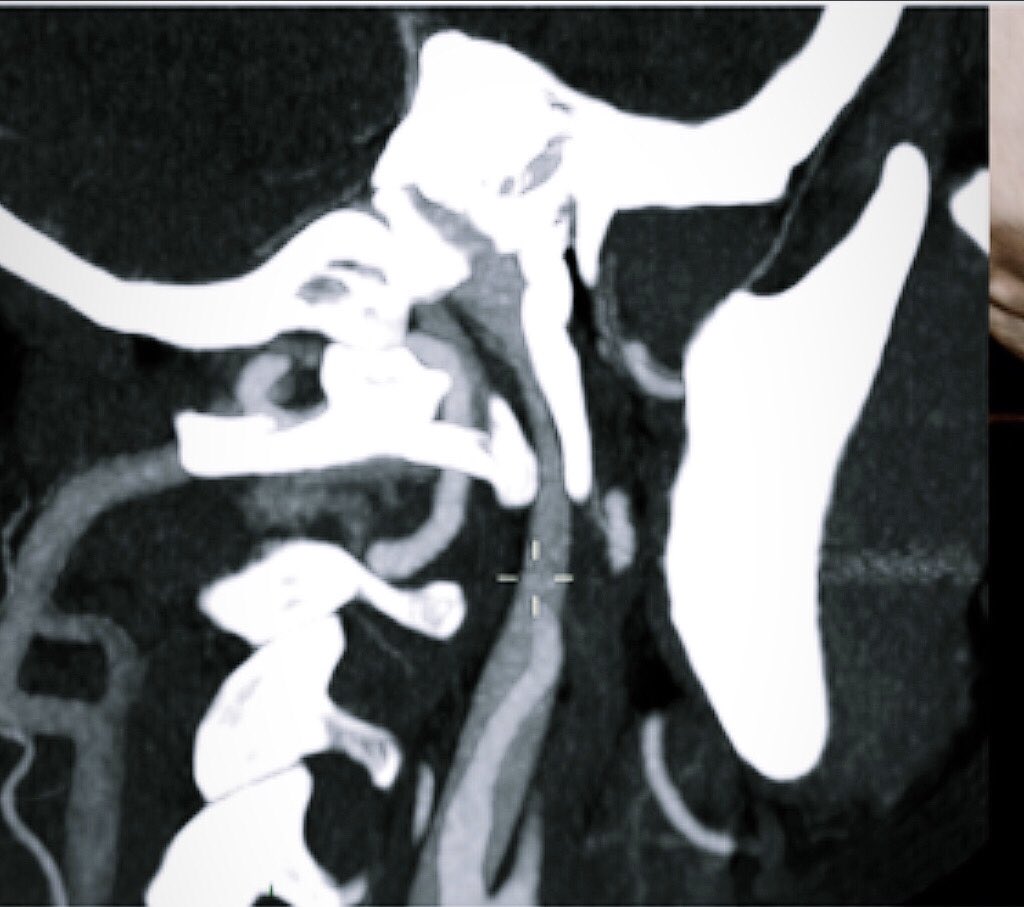

A #Vascular Nutcracker never been described so far. The eagle jugular syndrome | BMC Neurology | Full Text #CCSVI ⁦Alba Scerrati⁩ bmcneurol.biomedcentral.com/articles/10.11…

The #elongation of the #styloid #process may have different paths which creates #compression on the surrounding anatomical structures. There may be a possible association of #jugular #impingement by an elongated styloid process with symptoms. bmcneurol.biomedcentral.com/articles/10.11…

La terribile e mai descritta compressione della giugulare interna fra il processo stiloideo ed il processo trasverso della prima vertebra cervicale bmcneurol.biomedcentral.com/articles/10.11…